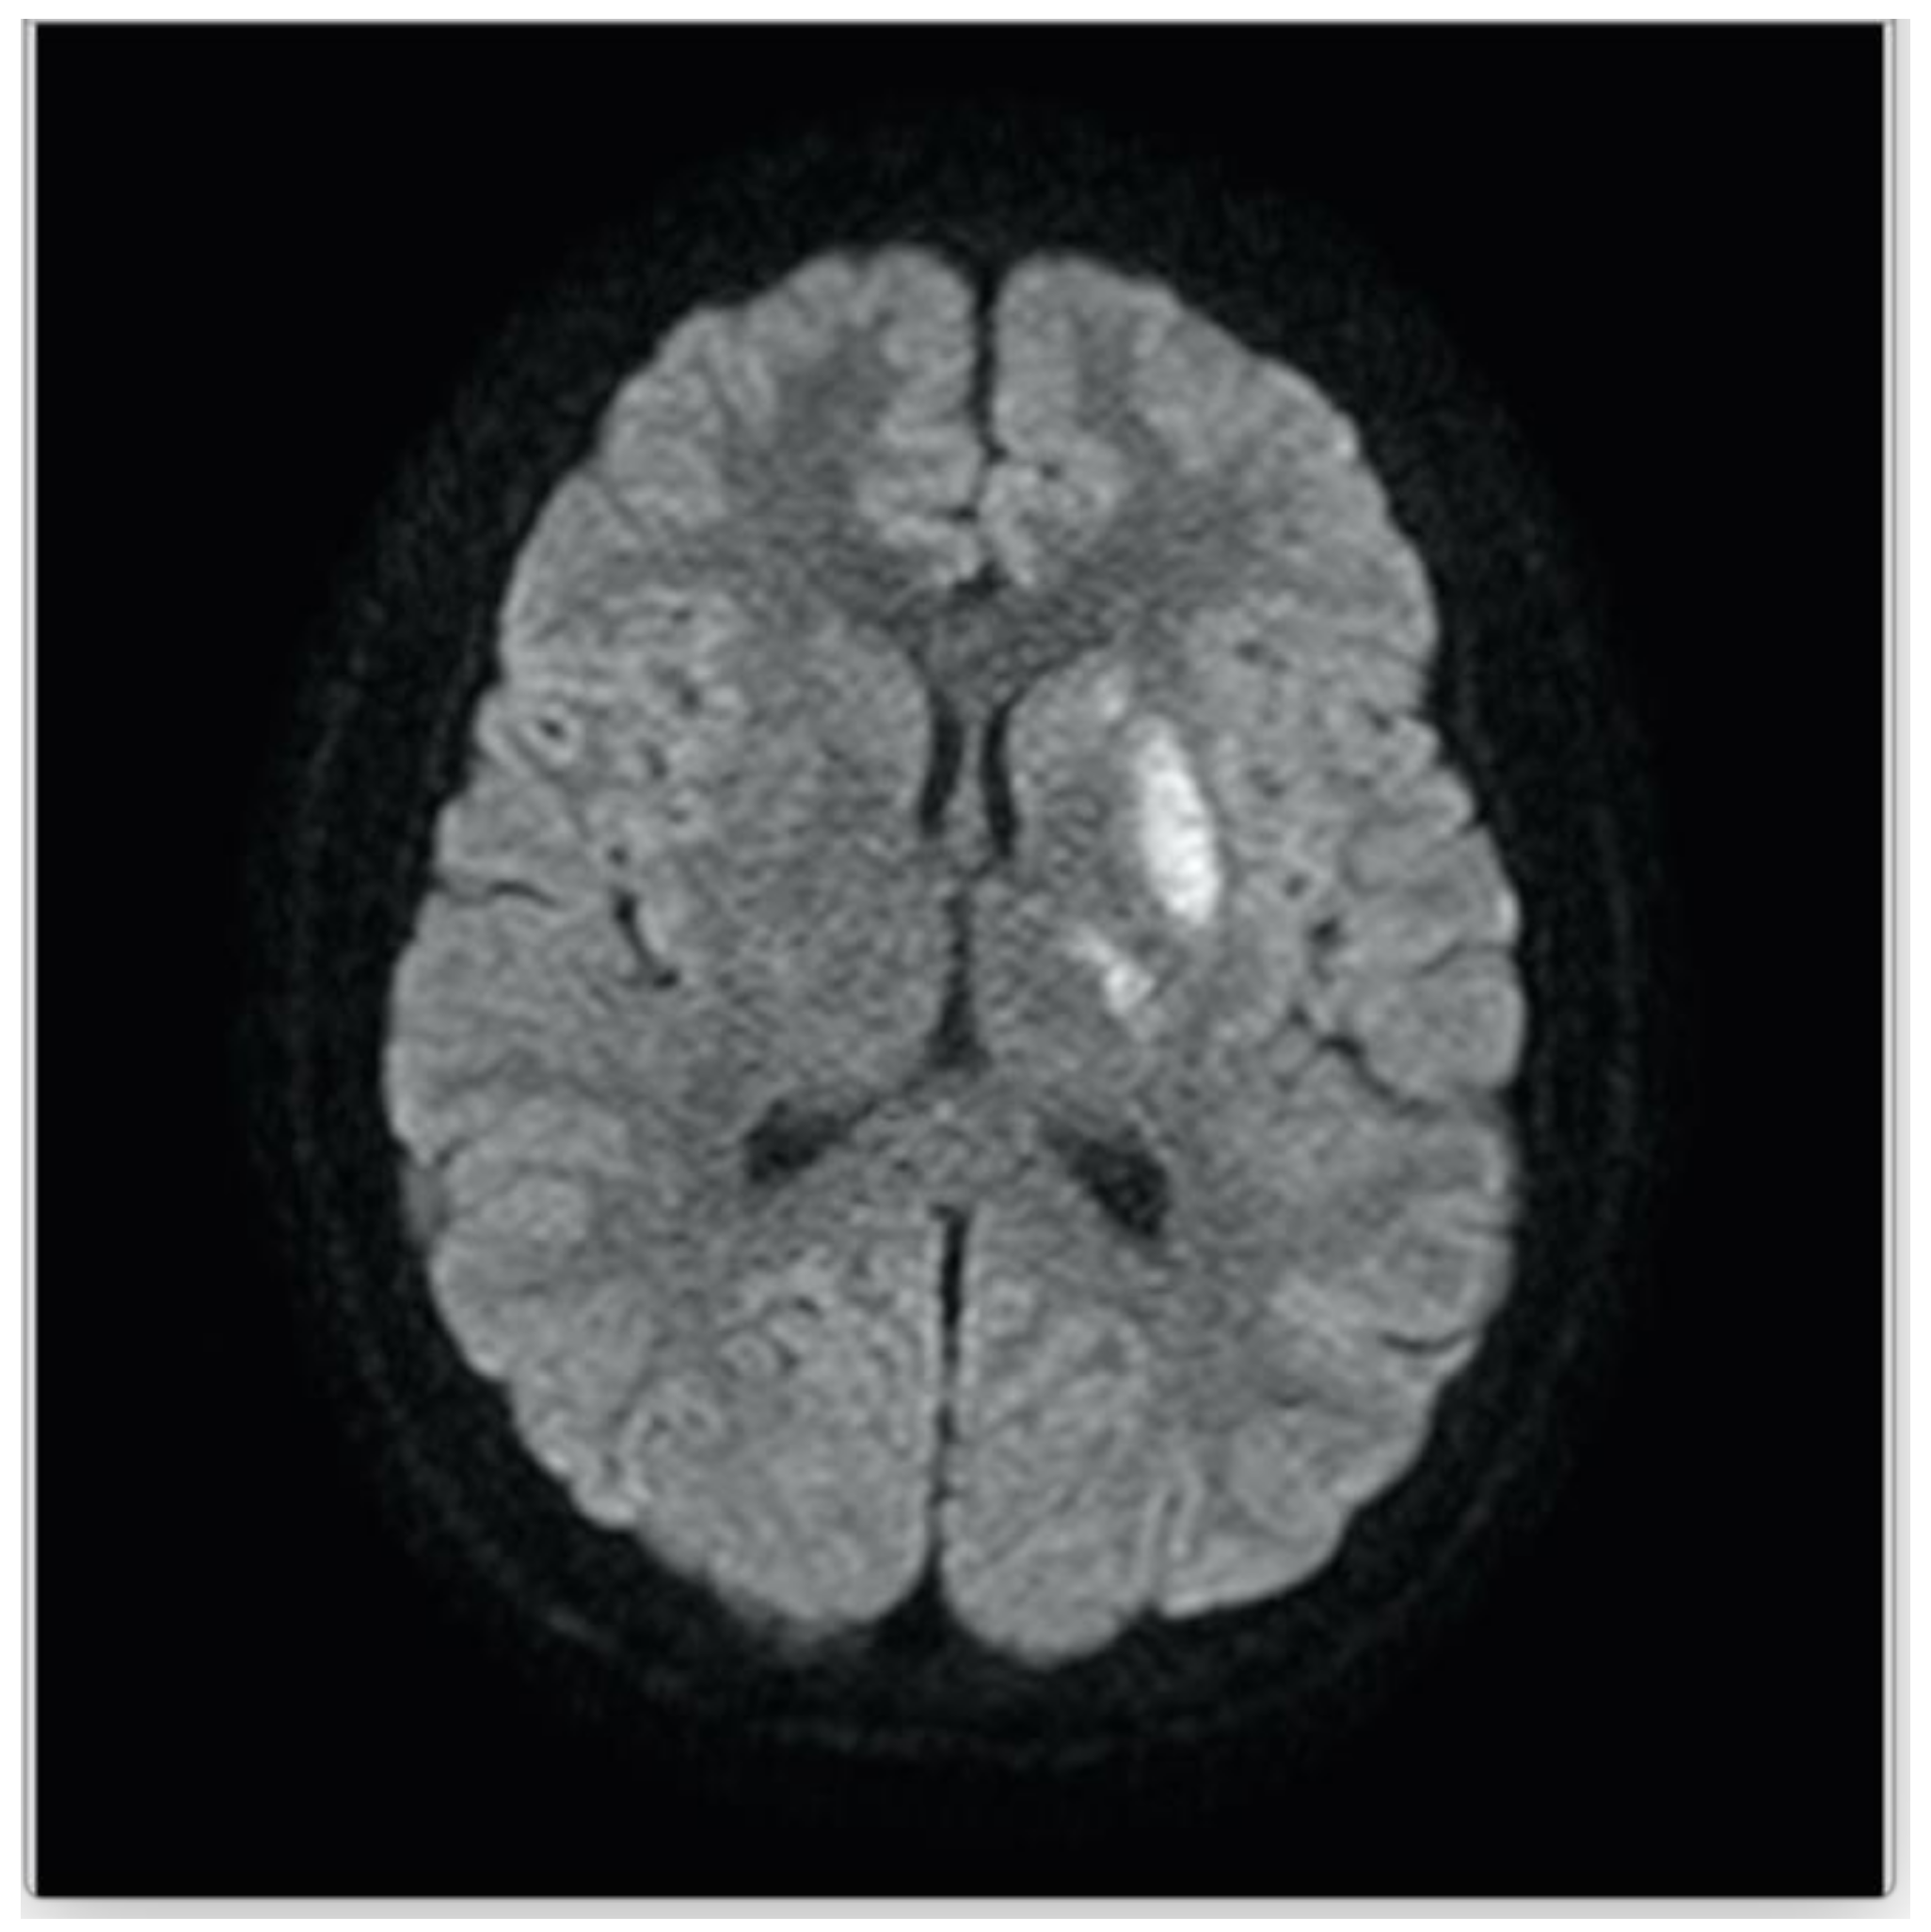

| Baumgartle * | 2016 | M/12 years old | Headache, facial drooping, slurred speech and right sided weakness | Left MCA infarction |